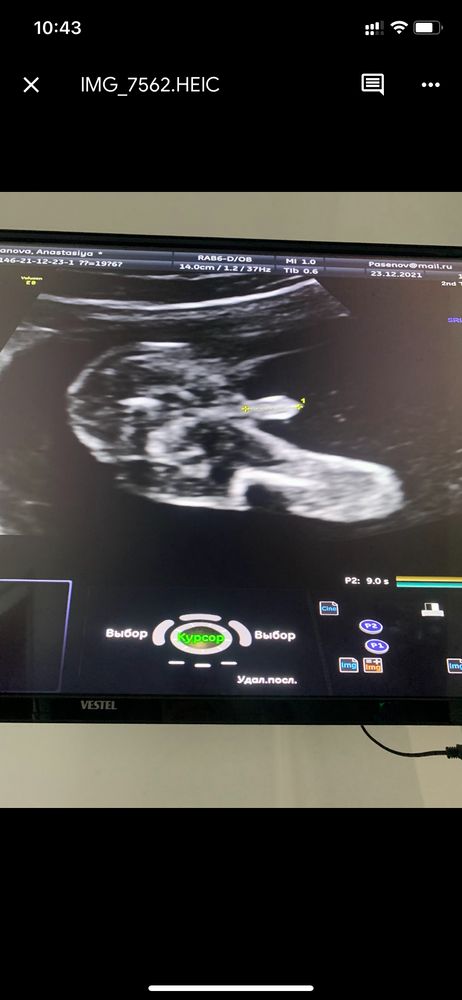

Девушки читала много про ошибки пола при этом на большом сроке )у нас же точно парень у девочек же не может быть такова меж ног ?😀у кого было в 16 и более недель так не ошиблись точно парень родился ?)

В 16 2 разных врача сказали и показали, а в 20 я попросила хотябы сфоткать 😂

Под большим сроком здесь подразумевается 25+ недель, когда все части тела уже довольно большие. А в норме в 16 недель всем говорят, так как это идеальный период для распознавания пола! У вас без сомнений Мальчик🌸

На фото, так-то, мальчик. А вообще, мало ли пуповина затесалась. Мне в 15 полных предположили парня, но не точно. УЗИстка была молодая, малоопытная - наверное, поэтому не ответила мне на 100%. В 18 полных на скрининге подтвердили мальчика.

У меня в 14,3 такая же точь в точь картина была на УЗИ с того де ракурса, сказали что точно тут уже 200% мальчик. Так и вышло)))